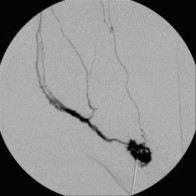

Perkutane Embolisation einer low-flow venösen Malformation (Gefäßmissbildung) der Fußsohle-1

(Bild 4 von 5)